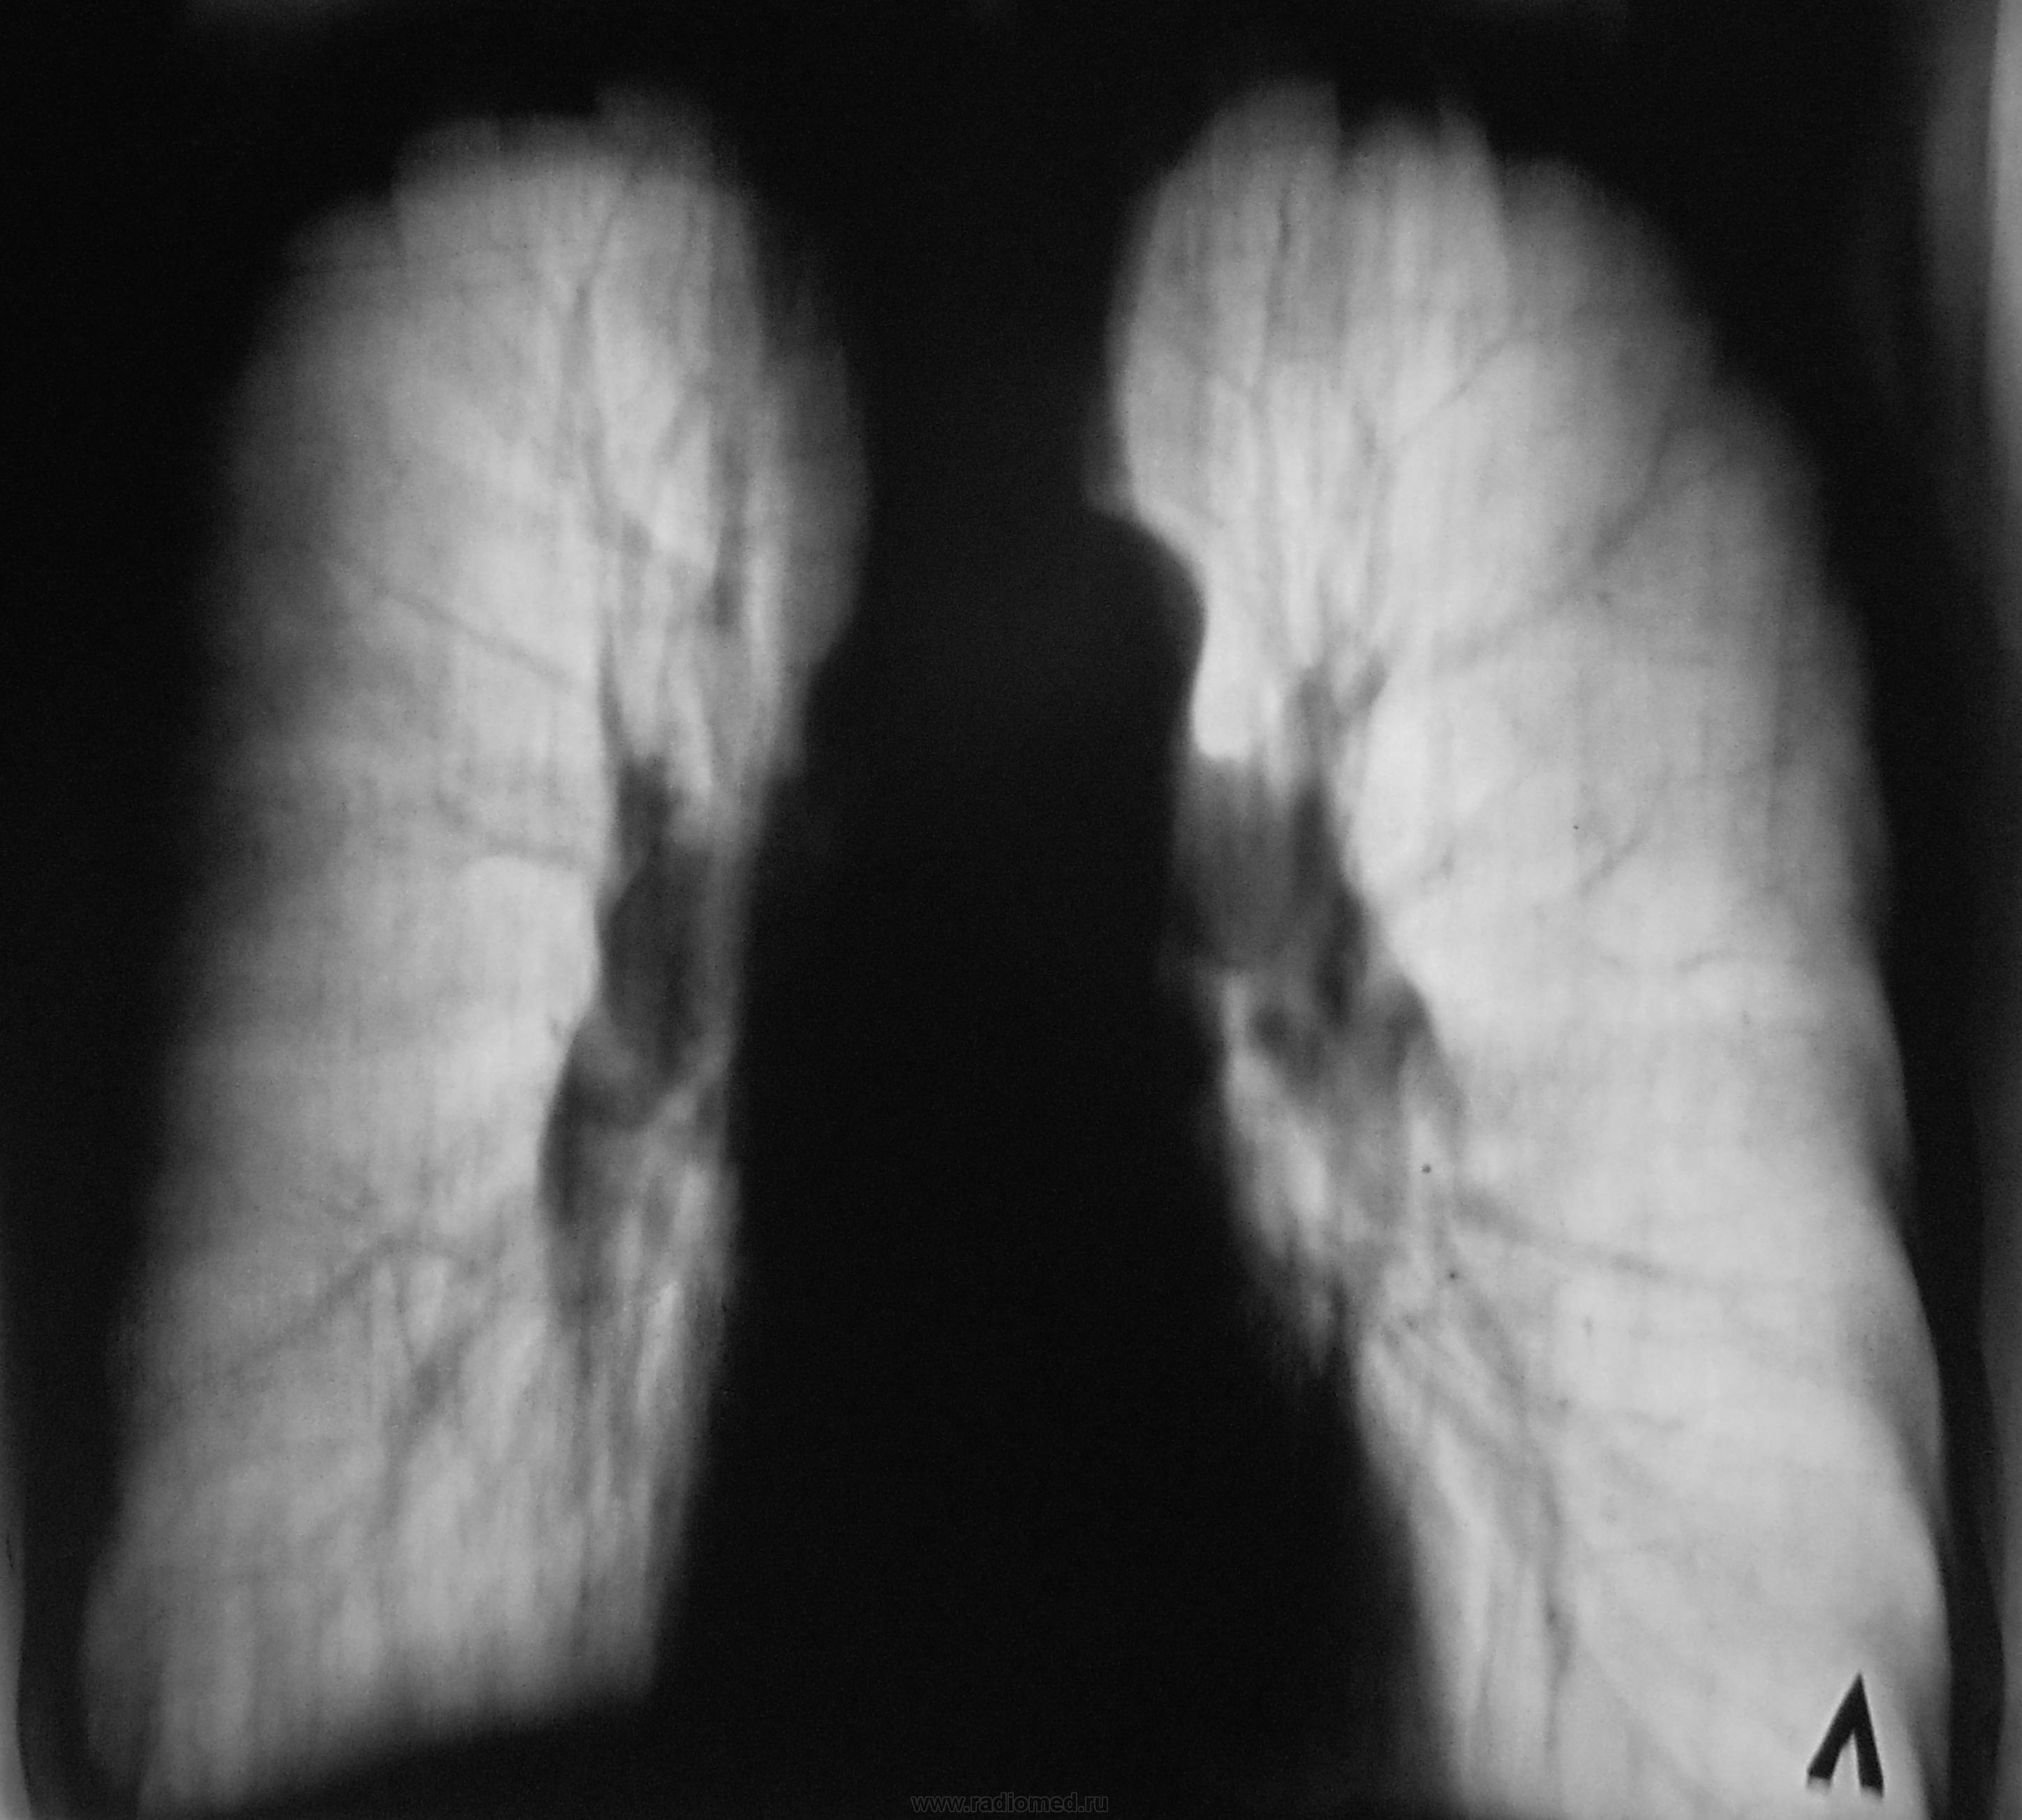

Срезы близки к срединному, а какой из них вентральный, какой дорзальный - не угадаю. Если первая пара "выше" второй, то я бы подумал на размазанное сочленение 1-го левого ребра с грудиной - мне кажется, он более кальцинирован.

Снимок №2 - более дорзальный (предположу 9-10 см), №3 - его обработка, №4 - более вентральный срез, №5 - его обработка. Валентин Львович, отчего же Вы брезгуете указать см на снимках. S1-2 слева и S10 справа кажутся "заплеванными". Синус справа облитерирован. Корни уплотнены. Эмфизема хороша. Плевро-перикардиальные спайки слева.